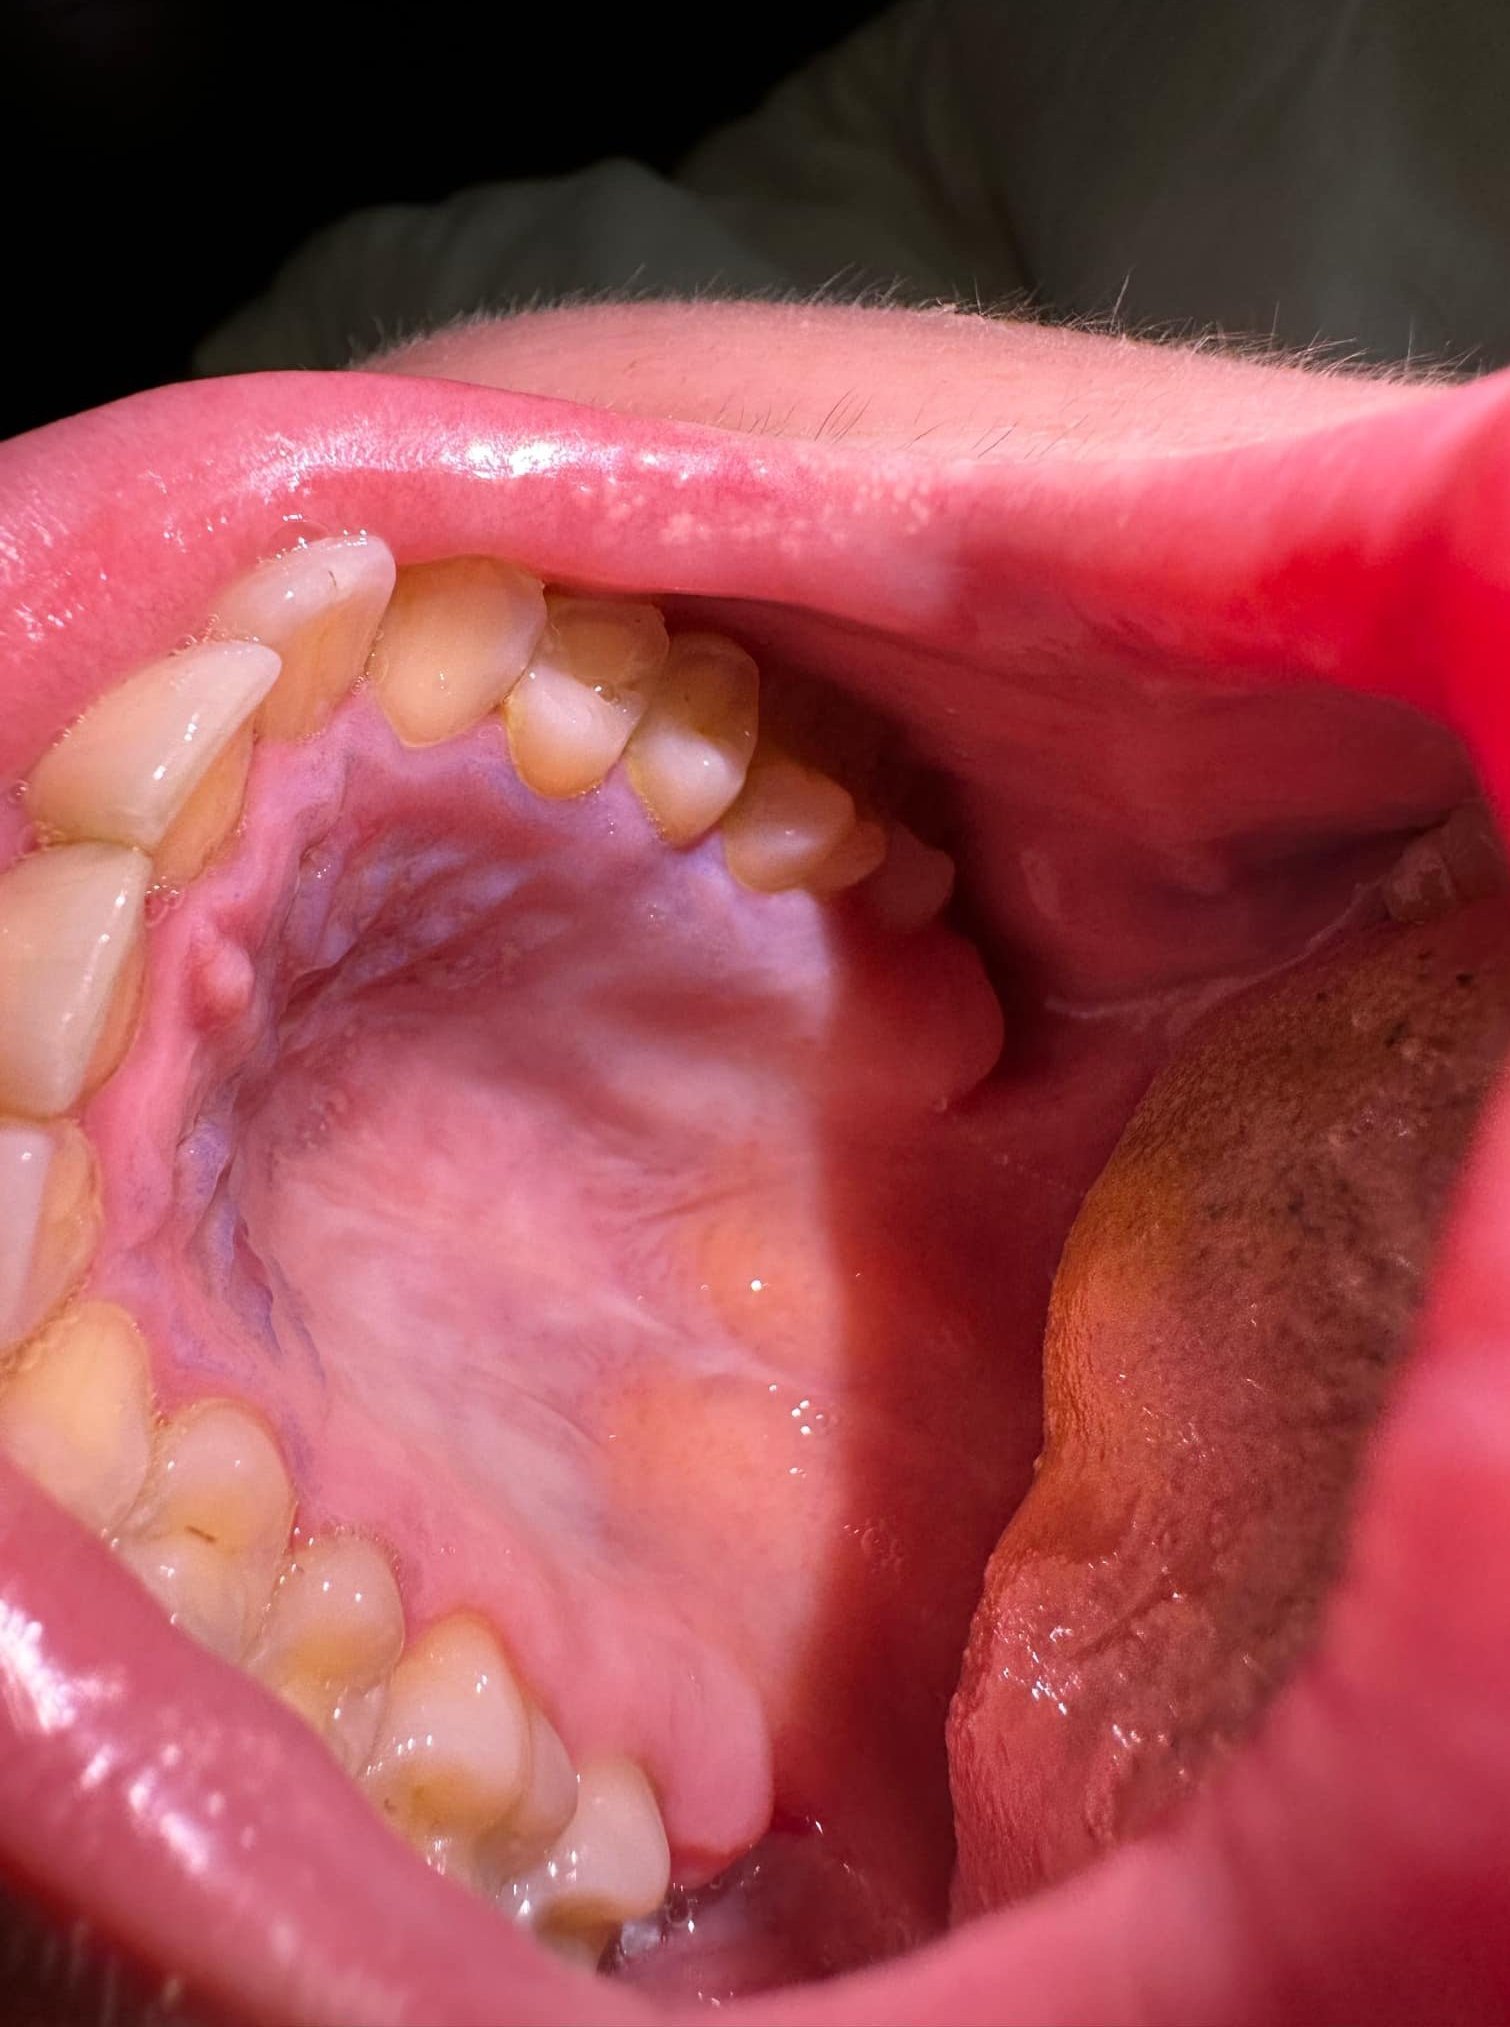

Здравейте,от близо седмица имам големи болки на небцето, и около венците горе в ляво.Ходих на зъболекар, на унг нито един от двамата не знае какво ми е.Мазах грануфорин,пръсках афтамил ,пих Нурофен и нищо.Сега съм на нещо като експериментално лечение.Не мога да се храня,пия вода със сламка.външно  не изглежда като нещо сериозно но е мн болезнено.ще прикача снимка и моля за мнение. Има следи от гранофурин на снимката.Благодаря

Най-добре потърсете друг добър зъболекар. Не знам точно какво визирате, че не изглежда толкова зле. Аз различавам синьо по небцето, което на мен не ми изглежда изобщо добре. Възможно е да събрана кръв, може друго да е, но със сигурност има причина за болката. Можете и кръвни изследвания да си пуснете - 100% ще излезе, че има възпаление в тялото.

Синия цвят е от гранофурина,оказа се херпес